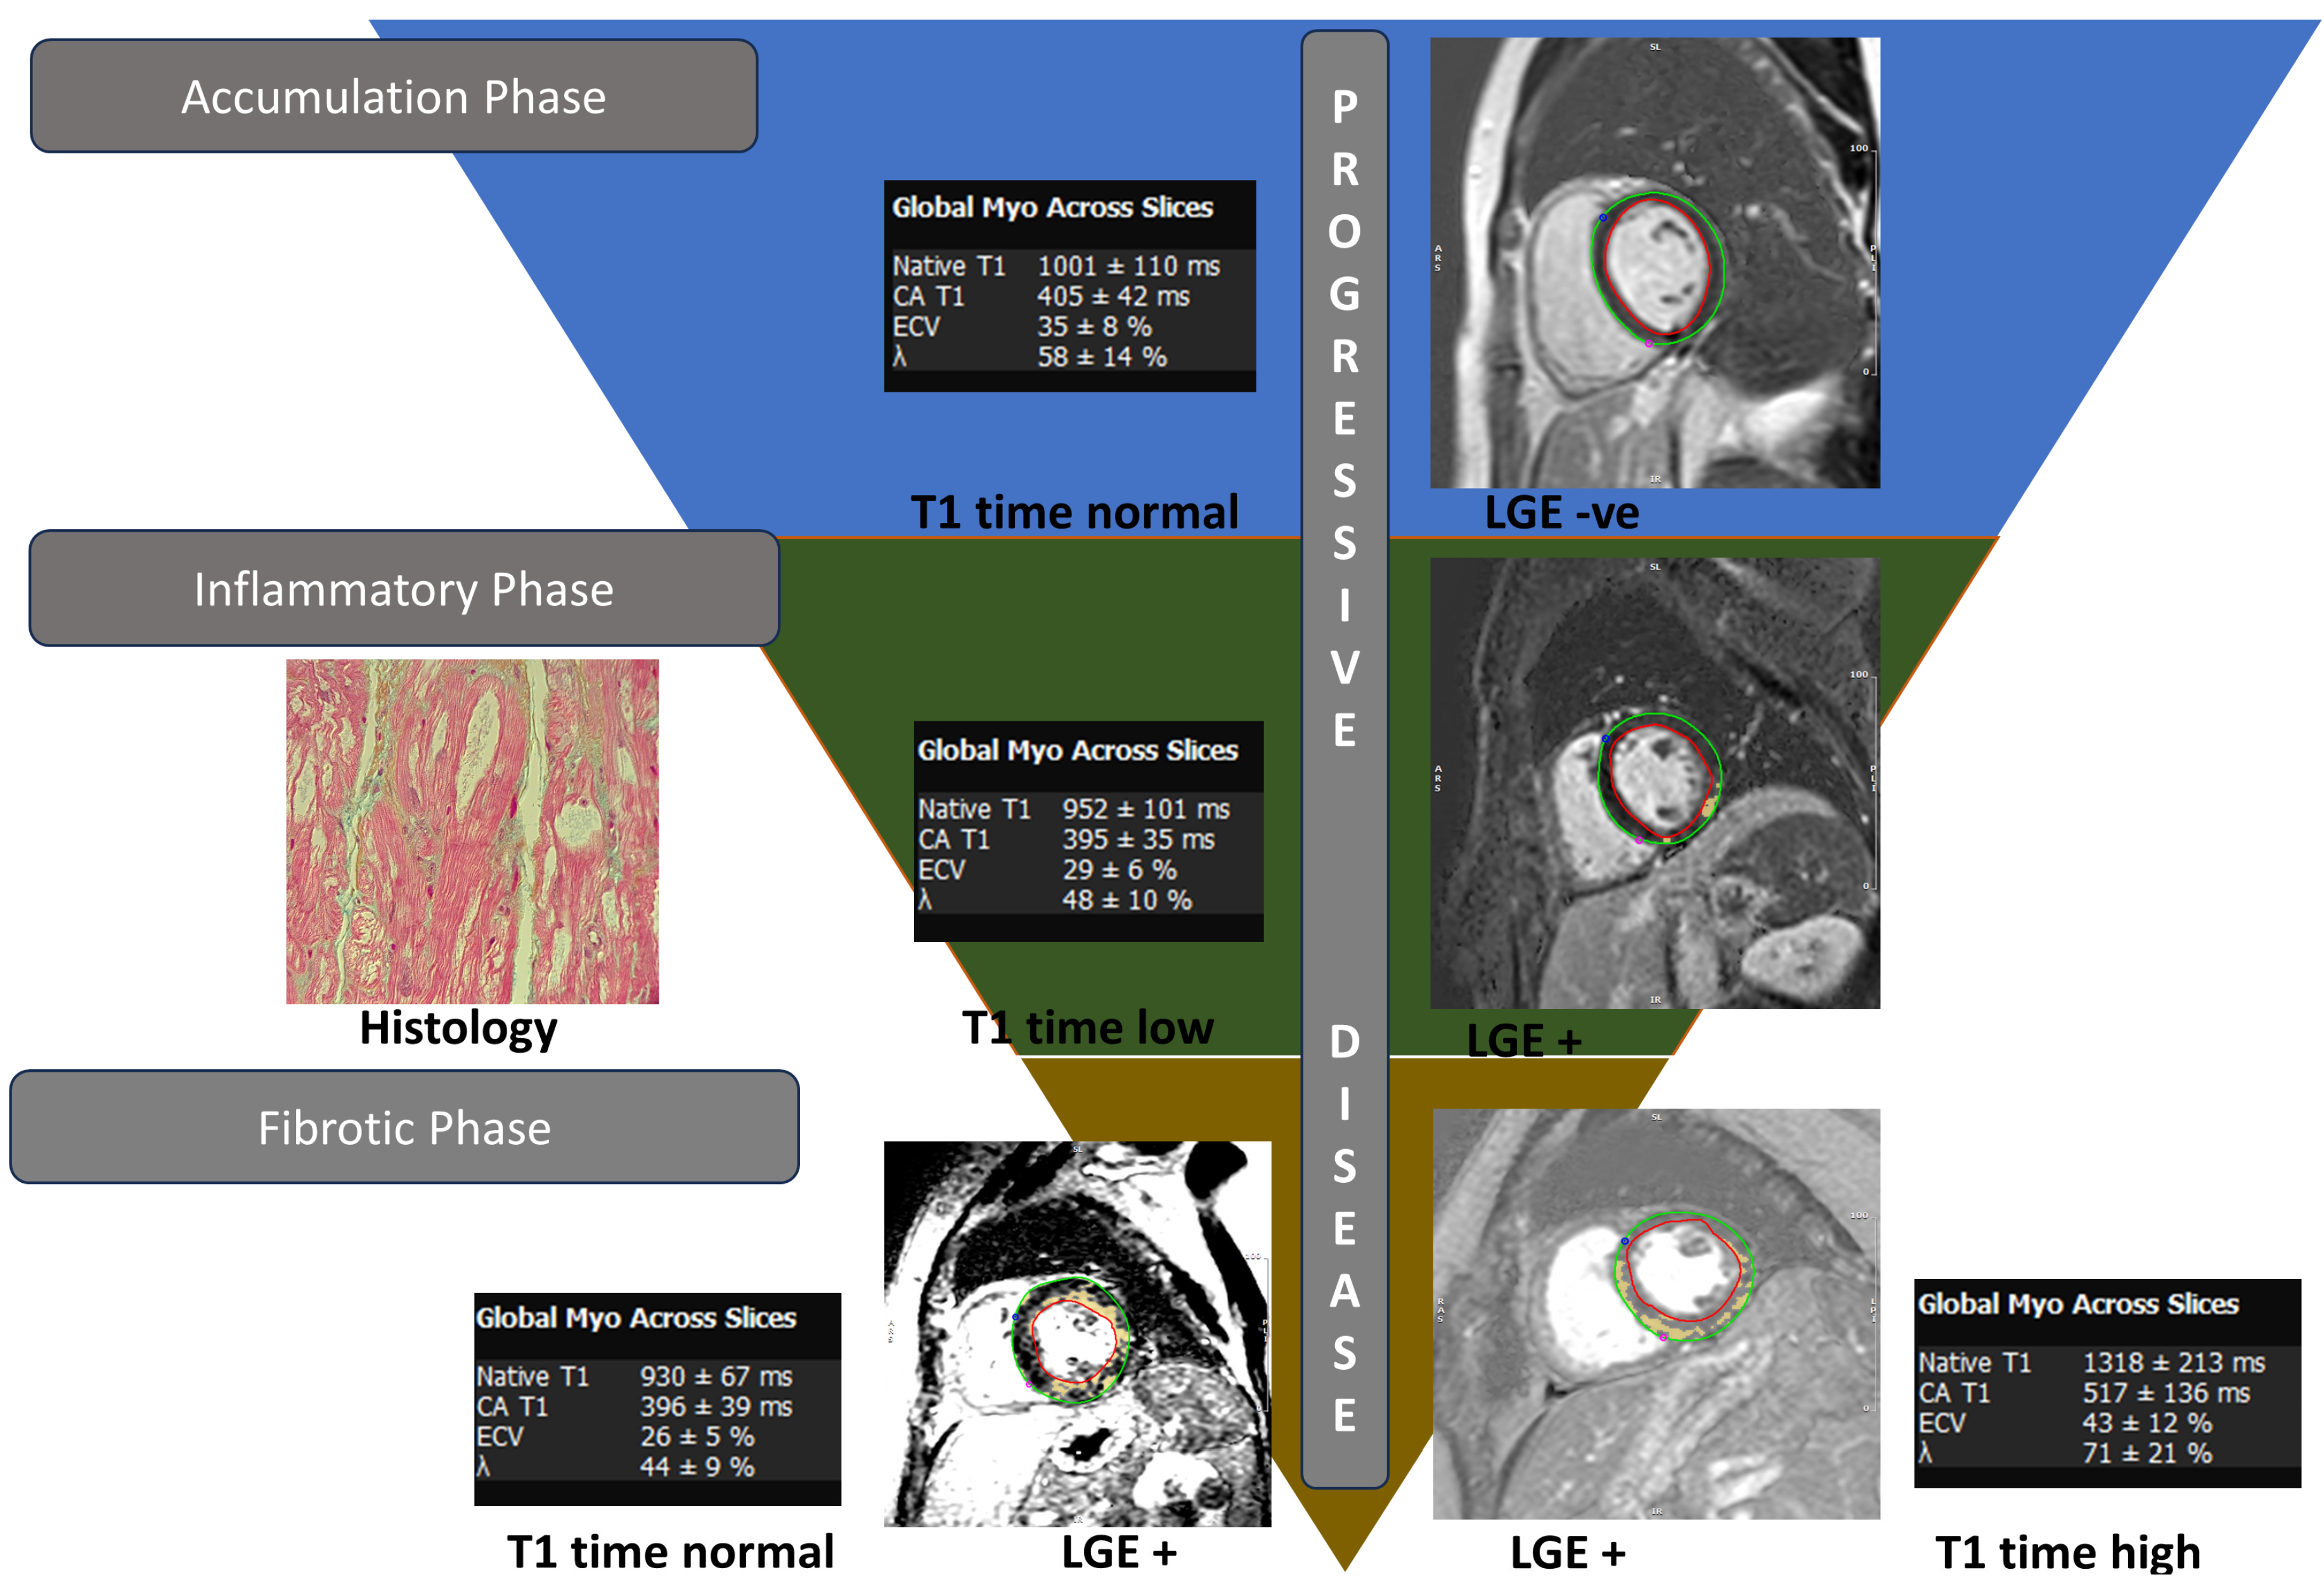

3.3. Cardiac Magnetic Resonance Imaging

- Augusto, J.B.; Nordin, S.; Vijapurapu, R.; Baig, S.; Bulluck, H.; Castelletti, S.; Alfarih, M.; Knott, K.; Captur, G.; Kotecha, T.; et al. Myocardial Edema, Myocyte Injury, and Disease Severity in Fabry Disease. Circ. Cardiovasc. Imaging 2020, 13, e010171. [Google Scholar] [CrossRef] [PubMed]

- Sado, D.M.; White, S.K.; Piechnik, S.K.; Banypersad, S.M.; Treibel, T.; Captur, G.; Fontana, M.; Maestrini, V.; Flett, A.S.; Robson, M.D.; et al. Identification and assessment of Anderson-Fabry disease by cardiovascular magnetic resonance noncontrast myocardial T1 mapping. Circ. Cardiovasc. Imaging 2013, 6, 392–398. [Google Scholar] [CrossRef] [PubMed]

- Nordin, S.; Kozor, R.; Bulluck, H.; Castelletti, S.; Rosmini, S.; Abdel-Gadir, A.; Baig, S.; Mehta, A.; Hughes, D.; Moon, J.C. Cardiac Fabry Disease with Late Gadolinium Enhancement Is a Chronic Inflammatory Cardiomyopathy. J. Am. Coll. Cardiol. 2016, 68, 1707–1708. [Google Scholar] [CrossRef] [PubMed]